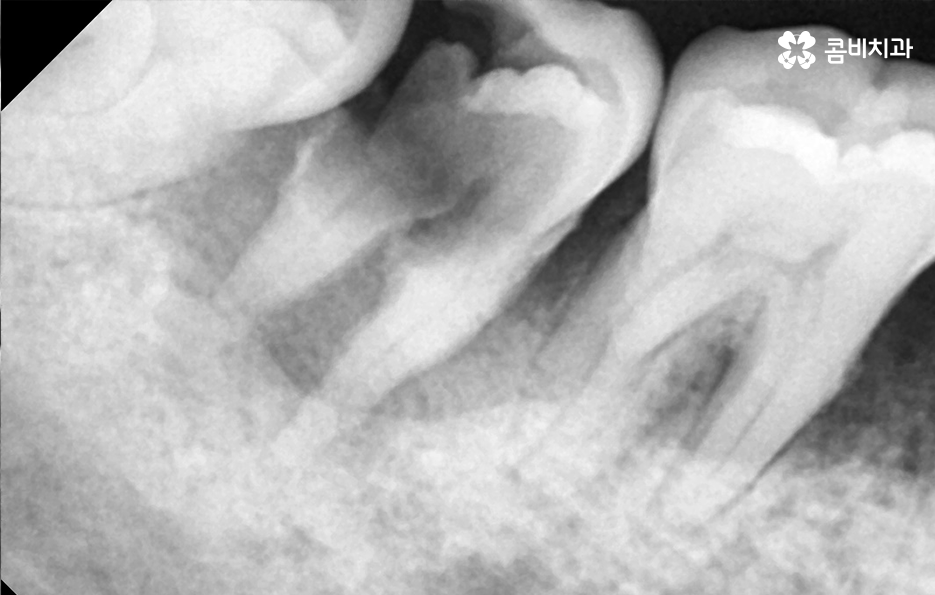

치주염으로 인해 치아를 잃게 되신 분들은 잘 아시겠지만 잇몸이 퇴축되어 있고 잇몸 뼈가 부족하여 임플란트 치료 과정 상에 뼈이식이 필요한 경우가 많고 치아를 한꺼번에 여러 치아를 잃게 되어 임플란트를 여러 개 심어야 하는 경우도 많을 거예요

임플란트의 치료 원리를 살펴보면 임플란트는 잇몸 뼈에 심고 골 유착 과정을 통해서 저작력을 얻기 때문에 치료 전과 치료 후 모두 잇몸 상태가 매우 중요한 치료라는 것을 알 수 있어요